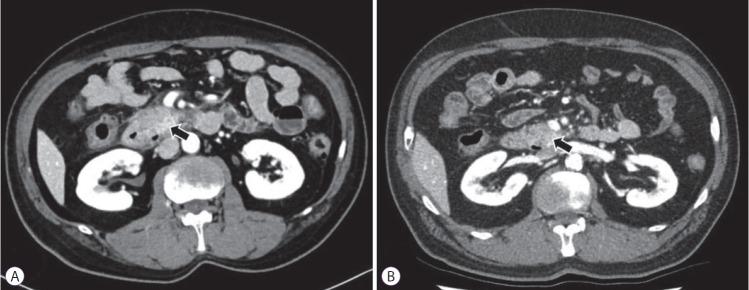

内镜超声引导下乙醇消融胰腺囊肿后坏死性胰腺炎所致十二指肠狭窄:一例报告

Duodenal Stricture due to Necrotizing Pancreatitis following Endoscopic Ultrasound-Guided Ethanol Ablation of a Pancreatic Cyst: A Case Report.

The frequency of incidental detection of pancreatic cystic lesions (PCLs) is increasing because of the frequent use of cross-sectional imaging. The appropriate treatment for PCLs is challenging, and endoscopic ultrasound-guided ablation for PCLs has been reported in several studies. Although the feasibility and efficacy of this therapeutic modality have been shown, the safety issues associated with the procedure are still a concern. We present a case of a 61-year-old man who underwent ultrasound-guided ethanol ablation for PCL and needed repeated endoscopic balloon dilatation for severe duodenal stricture caused by necrotizing pancreatitis after the cyst ablation therapy.

摘要

由于横断面成像的频繁使用,胰腺囊性病变(PCLs)的偶然检出率正在上升。PCLs的恰当治疗具有挑战性,并且在多项研究中已报道了内镜超声引导下对PCLs进行消融治疗。尽管已证明这种治疗方式的可行性和有效性,但与该操作相关的安全问题仍然令人担忧。我们报告一例61岁男性病例,该患者接受了超声引导下PCL乙醇消融治疗,在囊肿消融治疗后因坏死性胰腺炎导致严重十二指肠狭窄而需要反复进行内镜球囊扩张。